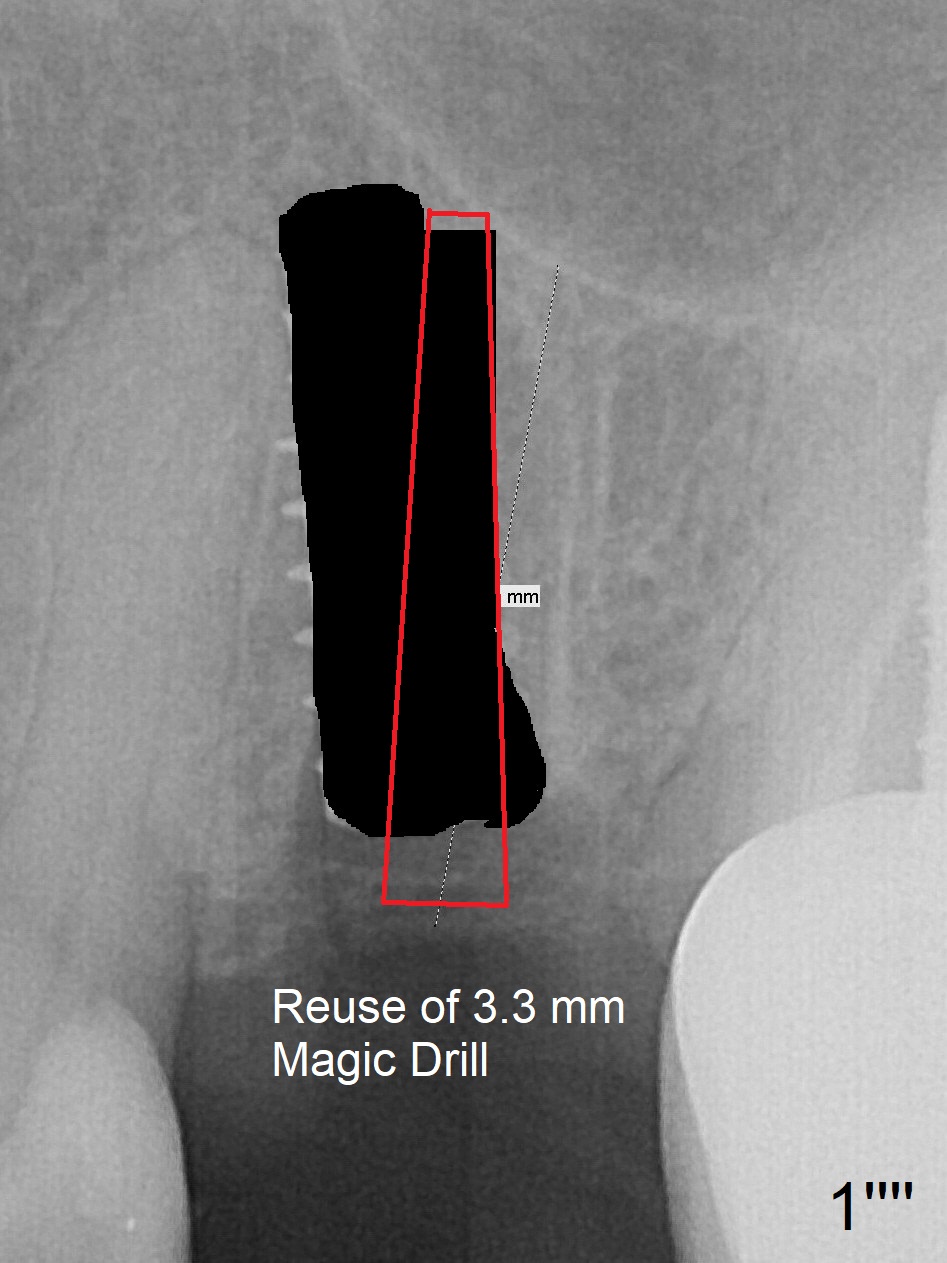

First, the implant is removed (Fig1'). Move the osteotomy distal by using Lindamann bur (Fig.1''). Remove the Lindamann bur (Fig.1'''). Reuse 3.3 m Magic Drill (Fig.1''''). After using Lindamann bur to move the osteotomy distal and reusing 3.3 mm drill, the trajectory of a 4.5x11 mm IBS dummy implant improves (Fig.2 with low stability).